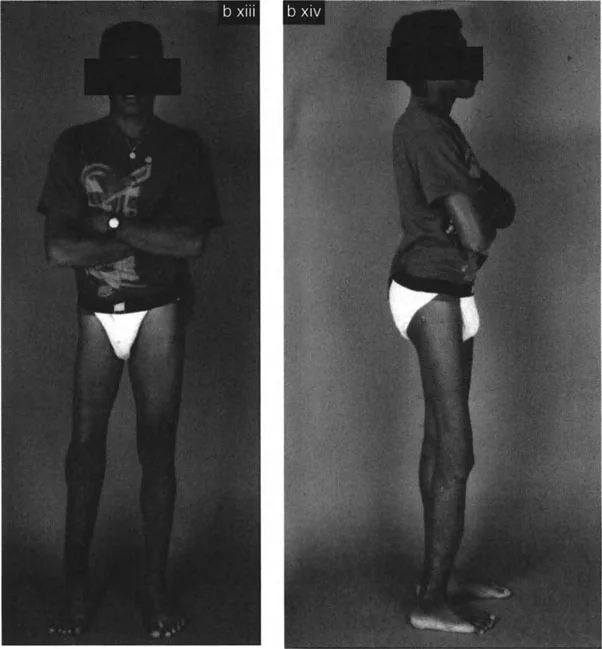

تغيير في مظهر الطرف

- تشوه مرئي في الساق: قد تبدو الساق ملتفة أو منحنية بشكل واضح عند النظر إليها.

- عدم تناسق في وضعية الجسم: قد يؤدي التشوه إلى ميل الحوض أو الكتفين، أو انحناء في العمود الفقري في محاولة لتعويض الخلل.

* نمط المشي (Gait Analysis): يلاحظ الدكتور هطيف كيف يمشي المريض، وكيف تتجه قدماه، ويقيم أي عرج أو عدم توازن.

* وضعية الطرف: يلاحظ أي التواء أو انحناء مرئي في الساق مقارنة بالجانب الآخر أو بالمعايير الطبيعية.